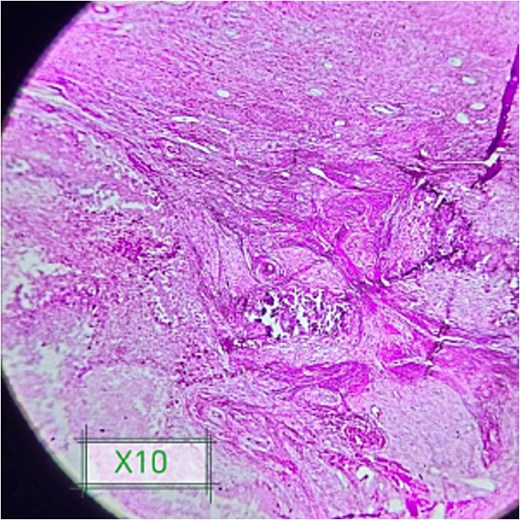

A punch biopsy from the calcified mass was carried out. Histopathological features typical for idiopathic tumoral calcinosis showed lobulated deposition of amorphous calcium with cystic space surrounded by foreign body giant cell reaction with chronic inflammatory cells without any features of malignancy or inflammatory reaction.

The patient underwent wide surgical excision of the mass under spinal anesthesia; it was completely removed without complications (Fig. 2). The histopathological results from the excised tissue showed features of idiopathic tumoral calcinosis with large, calcified deposits encapsulated by fibrous tissue, without features of malignancy or infection (Fig. 3).

Shows foci of amorphous calcium deposits surrounded by foreign giant cells and fibrosis.